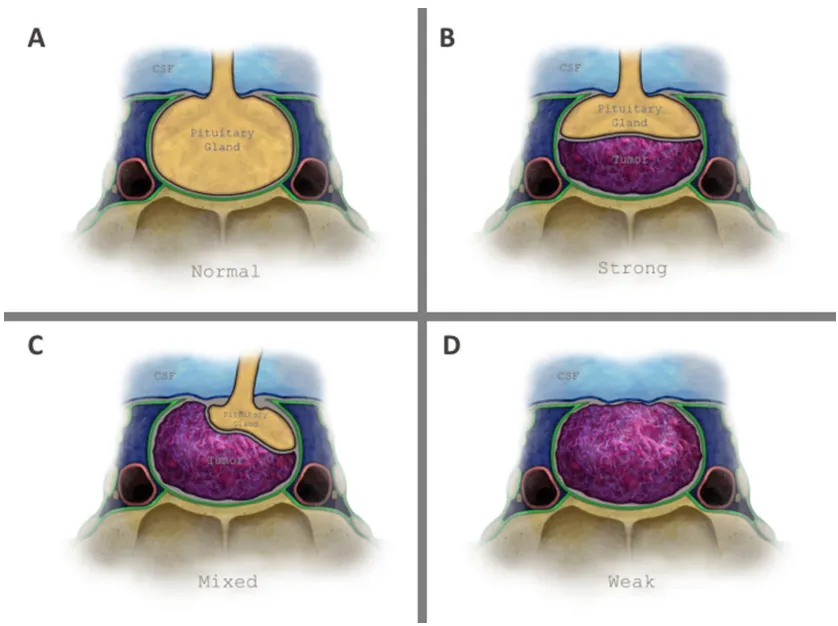

垂体肿瘤与鞍上脑脊液之间的界面由三层结构组成:蛛网膜组织(作为唯一恒定结构)、鞍隔硬脑膜以及垂体腺(图1a)。基于此解剖基础,福教授在前期研究中通过脑磁共振成像定义了两种鞍隔屏障亚型:薄弱型与强韧型,后续研究进一步提出了混合型屏障的概念(图1b-d)。

图1展示垂体窝顶壁解剖结构及鞍隔屏障分型示意图。

a部分显示无肿瘤状态下的正常解剖结构;b部分展示强韧型鞍隔屏障,其中垂体腺和/或硬脑膜位于肿瘤与脑脊液之间,图示案例为单纯由垂体腺构成的强韧型屏障;c部分为混合型鞍隔屏障,肿瘤部分区域直接接触蛛网膜下腔,部分区域接触垂体腺;d部分为薄弱型鞍隔屏障,肿瘤与鞍隔顶壁全界面直接接触蛛网膜下腔。